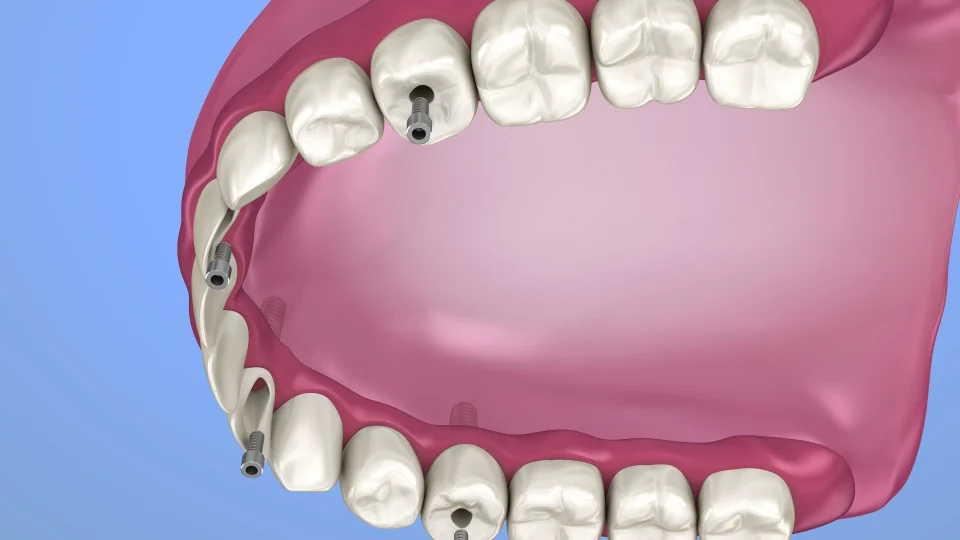

The process begins with a CAT scan of the jawbone. This scan generates a 3D digital model used in specialized software to plan the implant placement virtually. As a result, surgery is more accurate, and patient chair time is significantly reduced.